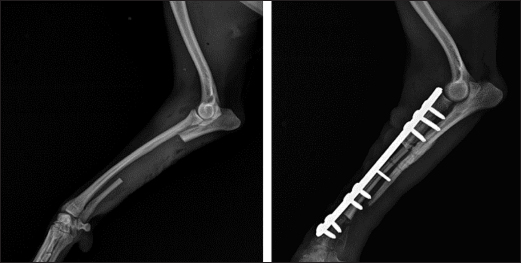

Fig. 5. Left—mediolateral radiograph of antebrachial bones 12 weeks after the revision surgery after the removal of screws from the cortical autograft; Right—mediolateral radiograph by the 15th week demonstrating complete union of the radial fracture and bone callus remodeling.

After the second control examination by the 12th post-operative week, because of the good radiological and clinical outcome, the three screws in the cortical graft were removed, leaving only screws in the proximal and distal bone fragments. By the 15th week, due to excellent clinical outcomes, all implants were removed (Fig. 5).